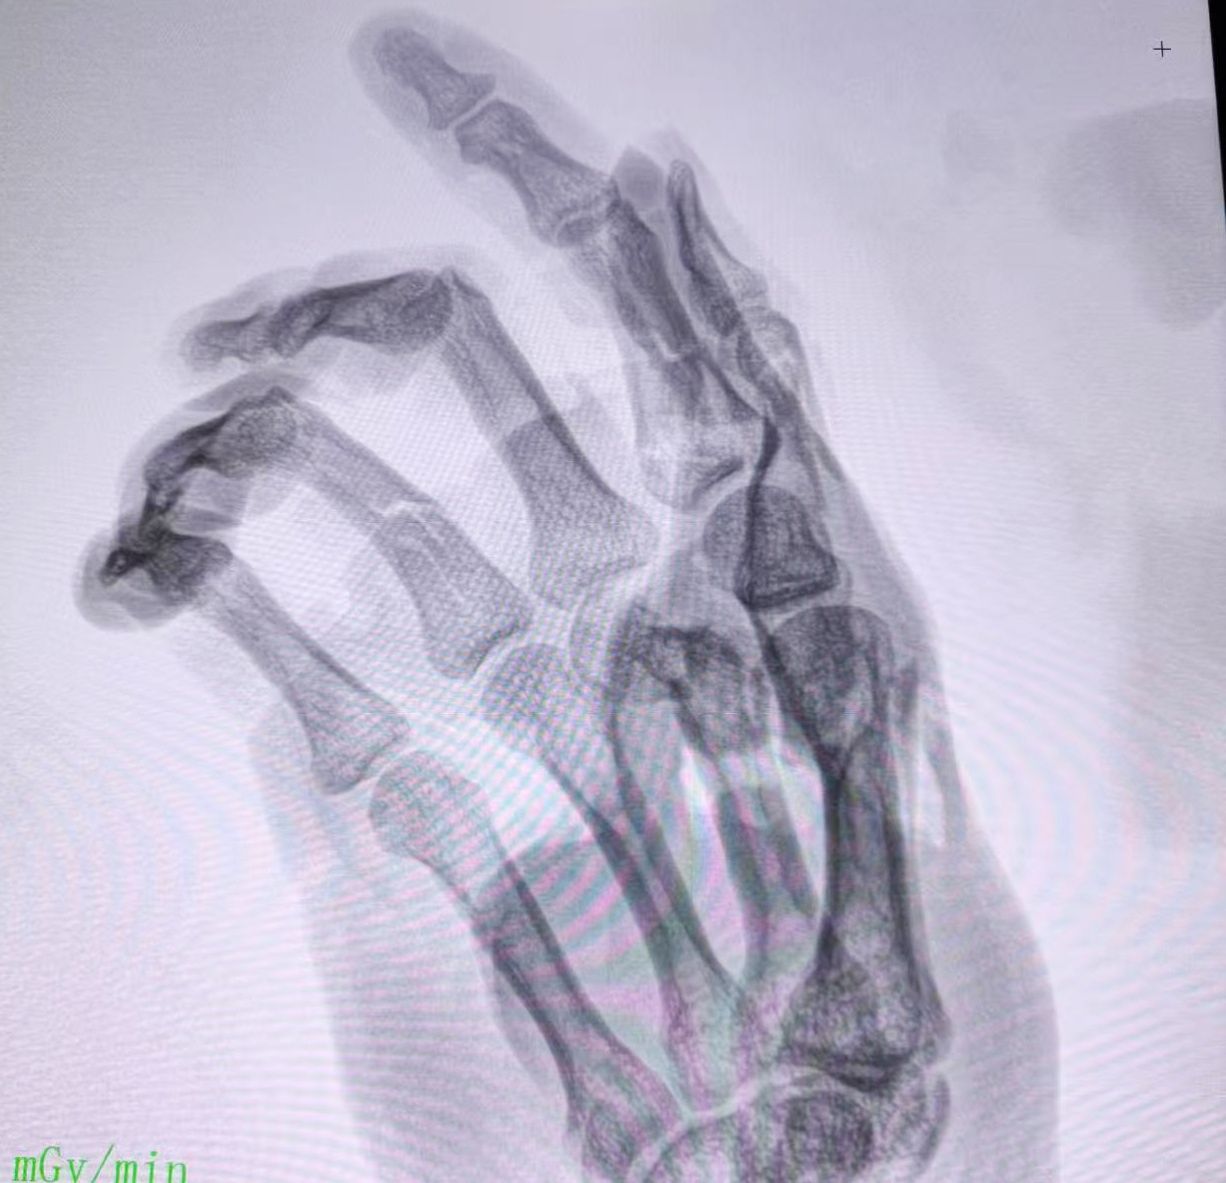

患者推入手术室后,消防员最大程度安全、零震动拆解了绞肉机器;麻醉科医生黄子原、吴思达等为患者进行插管全身麻醉和止痛镇静;手术室护士郭李君、杨鹏飞等为患者进行术前准备和手术配合;蔡宝塔团队采用掌骨骨折切开复位内固定术+各种深部组织感染清创术+石膏外固定术等手术方式,精准复位固定及低张力吻合神经,重建手指手掌关节功能,最大程度修复肢体功能。